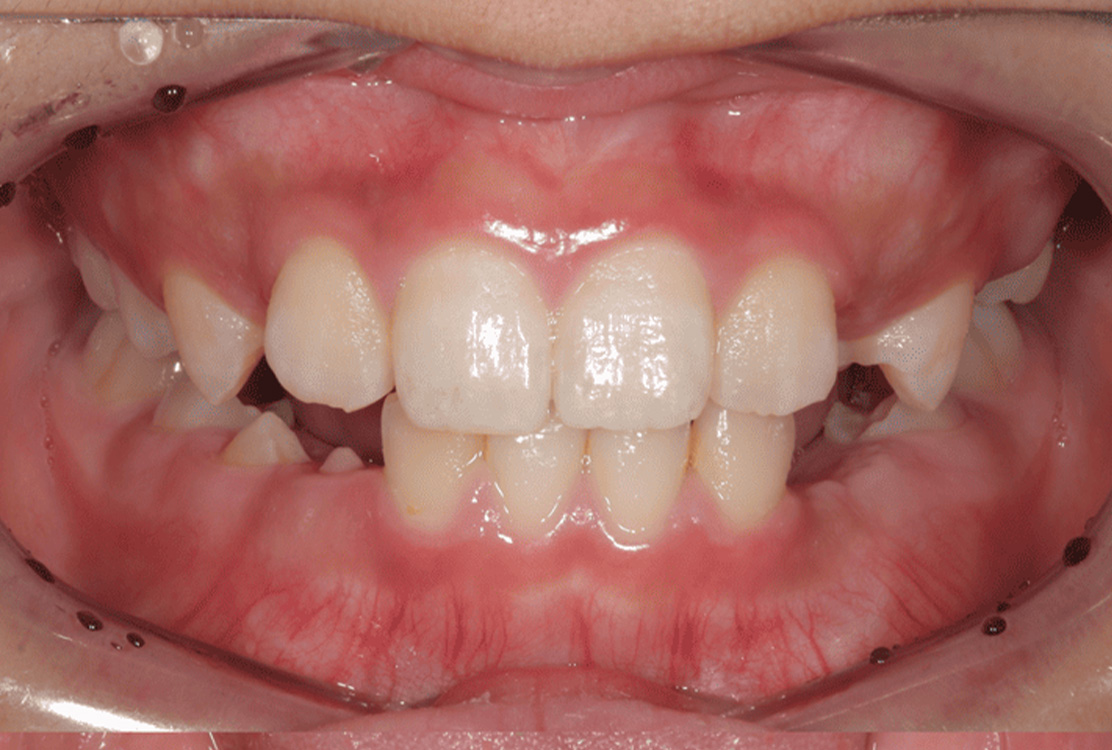

治療前

治療後